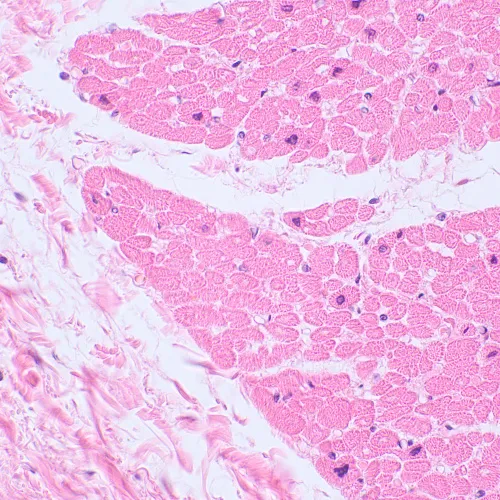

Биологичният микроскоп MAGUS Bio 230TL е съществен инструмент в лабораториите за санитарен контрол, така също в диагностичните и изследователските центрове. Микроскопът е с тринокулярна глава, има източник за преминаваща светлина (светодиоден) и е подходящ за наблюдение на полупрозрачни и прозрачни образци. В базовата конфигурация за наблюдения се използва методът на светлото поле. С допълнителни принадлежности могат да се използват методът на тъмното поле, с поляризирана светлина и с фазов контраст.

Цифрова камера с 2 МР сензор за изследване на микроскопични обекти чрез методите на тъмното или светлото поле. Камерата е снабдена с цветен CMOS сензор SONY Exmor с фоново осветление. То повишава светлочувствителността (2350 mV при 1/30 сек.) и подобрява качеството на изображението при слаба осветеност. Оптимални работни характеристики се постигат при работа с обективи с увеличения 40x, 60x и 100x.

• Работа по метода на тъмното и светлото поле с обективи с голямо увеличение: 40x, 60x и 100x